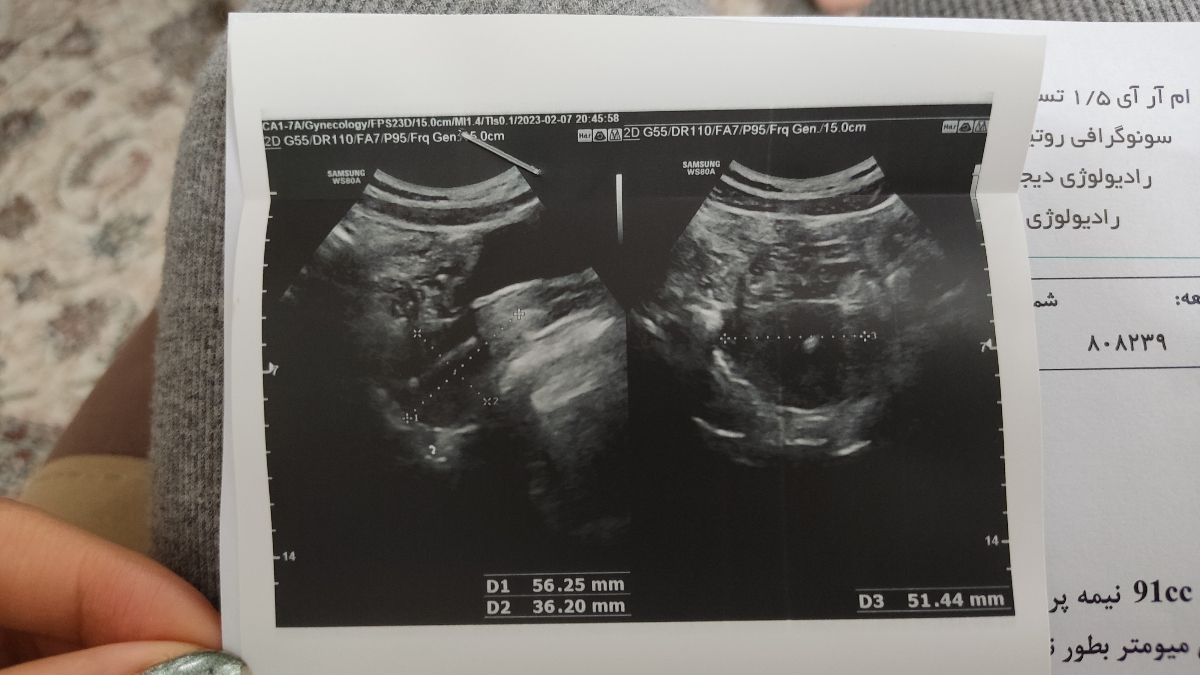

تفسیر سونوگرافی رحم و تخمدان

عزیزم مایع آزاد دیده شده در لگن میتواند بیانگر عفونت باشد حتما جهت ارزیابی مراجعه کنید. جایگاه iud مناسب است نگران نباشید.